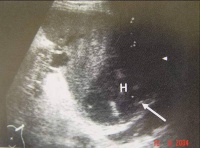

③x线检查:有选择的x线检查对腹部损伤的诊断是有帮助的。常用的有胸片、平卧位及左侧卧位腹部平片。立位腹部平片虽然更有意义,但不适用于重伤员。根据需要拍骨盆正、侧位片。

Bk8b8.jpg

• X线检查:常用胸片及平卧位腹平片

– 胃或肠管破裂à腹腔游离积气(如膈下)

– 腹膜后十二指肠或结直肠穿孔à腹膜后积气

– 肝破裂à右膈升高、肝正常外形消失、右下胸肋骨骨折

– 脾破裂à胃右移、横结肠下移、胃大弯有锯齿形压迹

大多数胃、十二指肠破裂和少数结肠、小肠破裂者,腹部平片显示膈下新月形阴影,提示有游离气体;侧卧位时的“穹窿征”和“镰状韧带征”,或仰卧位时的“双肠壁征”(在肠腔内外气体衬托下,肠管的内、外壁清晰可见),也是腹腔内积气的表现。为了提高阳性率,最好维持所需体位十分钟然后拍片。一般腹腔内有50ml以上游离气体时,X线片上便能显示出来。腹膜后十二指肠或结、直肠穿孔时,腹膜后有气体积聚,腹部平片上可见典型的花斑状阴影。肠间隙增大,充气的左、右结肠与腹膜脂肪线分离,是腹腔内积血量大的表现。腹膜后血肿时.腰大肌影消失。脾破裂时,可表现为胃向右移、横结肠向下移、胃大弯有锯齿形压迹(脾胃韧带内血肿)。右季肋部肋骨骨折、右膈抬高和肝正常外形消失,提示有肝破裂的可能。左侧膈疝时多能见到胃泡 或肠管突人胸腔。右侧膈疝诊断较难,必要时可作人工气腹以资鉴别。X线柱查可发现金属异物的部位,若与投射物的入口联系起来,可能有助于推测其在体内的轨迹以及可能伤及哪些脏器。 选择性血管造影对实质性器官破裂和血管损伤的诊断帮助很大。可见动脉相的造影剂外漏、实质相的血管缺如及静脉相的早期充盈。但血管造影要求的设备条件和技术条件较高,且属侵入性检查,有痛苦、费时和昂贵等缺点.绝大多数伤者不适合应用。